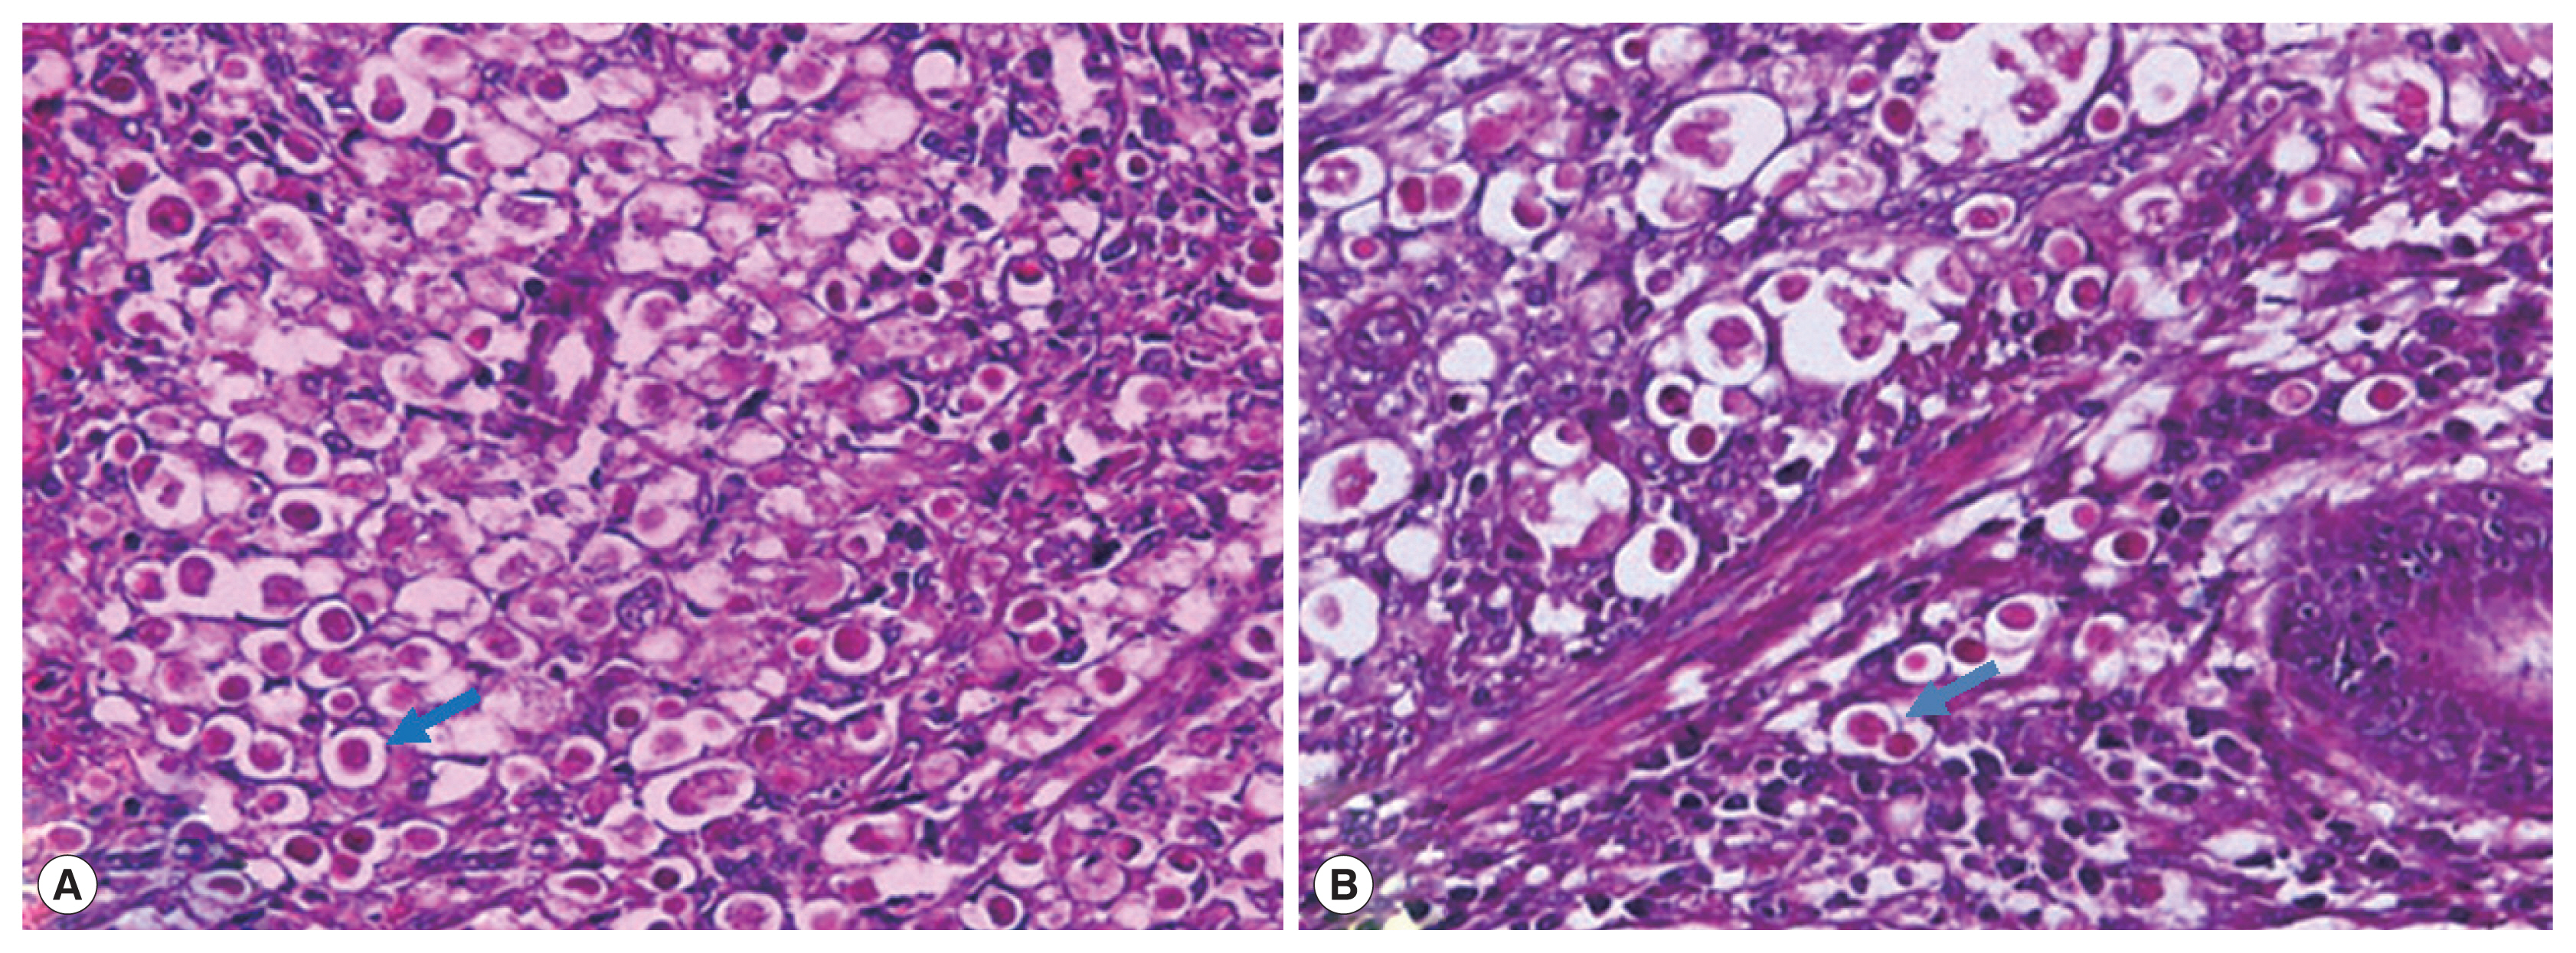

Histopathologic examination

Appropriate amounts of liver and cecal tissues were cut and observed in the hematoxylin and eosin stained tissue sections. Then, the sections were mounted with neutral balsam for microscopic examination. A large number of circular eosinophilic histomonad-like parasites appeared in the liver and cecal tissues (Fig. 2).